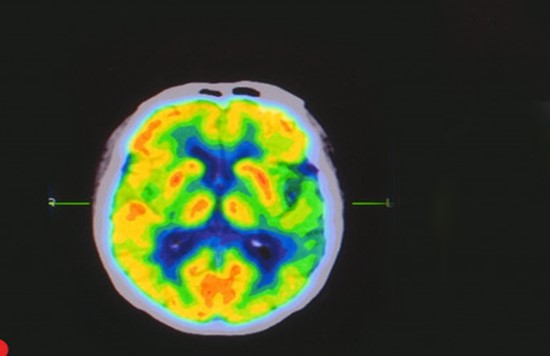

-Other applications of Compton Scattering include its use in the Compton Scatter Densitometer, which can be used to detect flaws or impurities in objects. Compton Scattering Imaging can measure the physical density of objects.